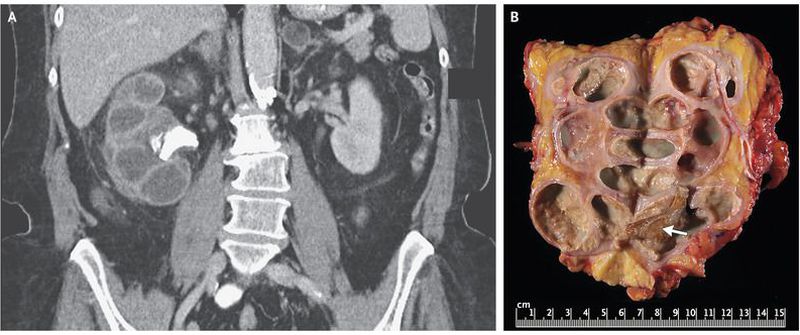

A 73-year-old woman presented to the emergency department with a 10-day history of fever and lethargy. Her medical history included type 2 diabetes, recurrent urinary tract infection, and weight loss of approximately 13.5 kg during the previous year. Laboratory studies revealed a white-cell count of 14,290 per cubic millimeter (reference range, 4500 to 11,000) and a serum creatinine level of 1.3 mg per deciliter (115 μmol per liter; reference range, 0.6 to 1.5 mg per deciliter [53 to 133 μmol per liter]); examination of the urine sediment revealed 50 to 100 white cells per high-powered field, but a culture was negative for bacteria. Computed tomography of the abdomen performed with the intravenous administration of contrast material (Panel A) revealed an enlarged right kidney with staghorn calculus in the ureteropelvic junction, cortical atrophy, and calyceal dilatation — an appearance referred to as a “bear paw sign.” Intravenous antibiotic agents were initiated, and percutaneous nephrostomy was performed. Culture of the drainage grew Proteus mirabilis. After a radionucleotide scan showed that renal function was absent on the right side, nephrectomy was performed. Gross pathological analysis showed a staghorn calculus (Panel B, arrow), dilated calyces, cystic cavities, and yellow tissue. Histologic testing revealed fibrosis and chronic granulomatous inflammatory infiltrate with lipid-laden foamy macrophages and necrotic debris. Xanthogranulomatous pyelonephritis was diagnosed. Xanthogranulomatous pyelonephritis, a form of chronic pyelonephritis, is typically associated with obstructing calculi and recurrent urinary tract infection. Complications may include abscesses and fistulae. Loss of renal function is common, and nephrectomy is the definitive treatment. The patient was discharged 5 days after surgery and was feeling well with stable renal function at 1 month of follow-up.